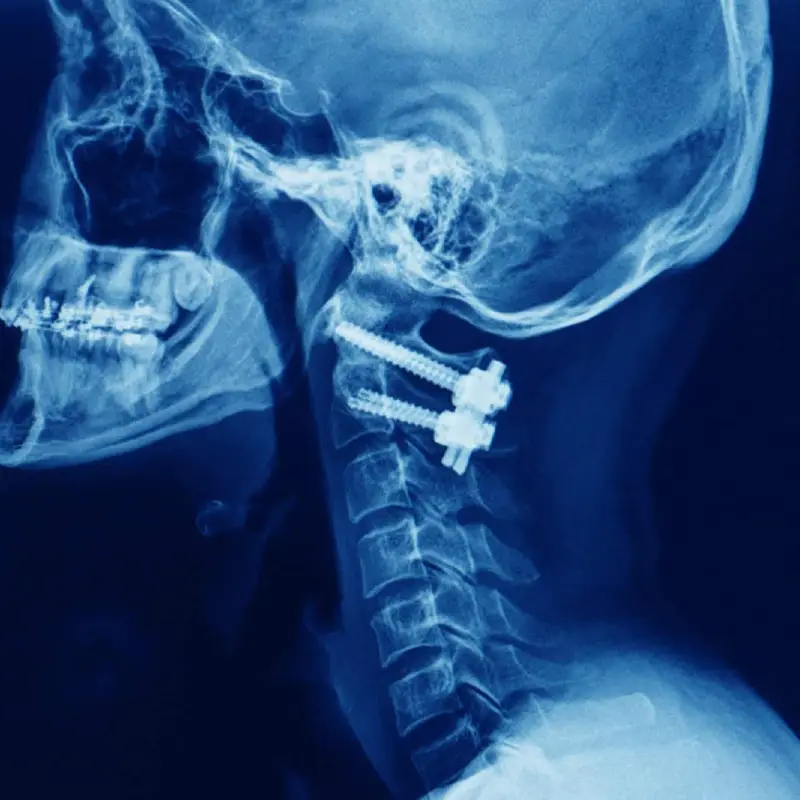

Anterior Cervical Discectomy And Fusion With Plating

C1-C2 Posterior Instrumented Stabilisation

C1-C2 Transarticular Screw